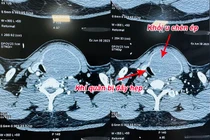

Bướu giáp thòng trung thất chiếm tỷ lệ nhỏ (3 – 20%) trong các trường hợp bướu giáp. Không chỉ xâm lấn hai thùy giáp, thực quản và khí quản, loại bướu này còn thòng xuống lồng ngực, chèn ép các mạch máu quan trọng...

Người bệnh bị bướu cổ hơn 30 năm với kích thước khối u tuyến giáp lớn, chèn ép, đẩy khí quản cổ sang một bên gây khó thở đã được các bác sỹ Bệnh viện Nhân dân Gia Định phẫu thuật thành công.

Bị u tuyến giáp lành tính to không mổ, đến khi nuốt vướng mới đến lại bệnh viện thì u vỡ, chèn ép khí quản, thần kinh thanh quản và thực quản gây nguy hiểm tới tính mạng.

Các bác sĩ Bệnh viện TWQĐ 108 vừa phẫu thuật thành công khối u tuyến giáp khổng lồ với kích thước thùy phải 10x6cm, kích thước thùy trái 12x7cm, phát triển cả lên phía trên và đẩy xuống nền cổ, gây đè hẹp khí quản.